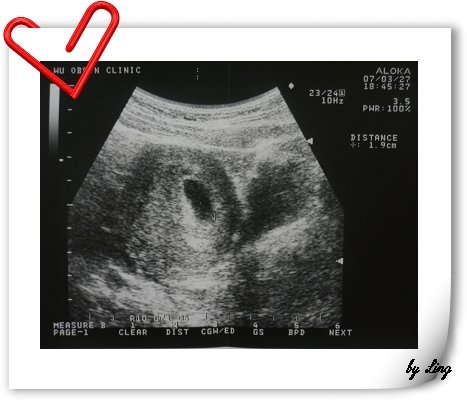

這是我BABY在5週時的胚囊超音波,大約1.9CM∼

放心,

BABY會長得很快喔~~~

15w2d的ling